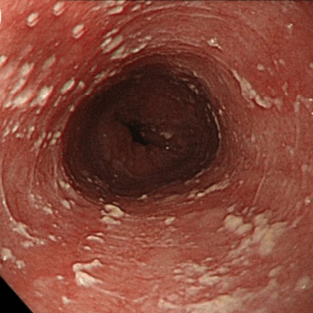

Эндоскопическая классификация кандидозного эзофагита по Kodsi

Степень III: Сливные линейные и узловатые приподнятые бляшки, с гиперемией и язвами